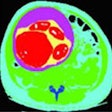

Case report: Conjoined twins -- thoraco-omphalopagus (type A)

December 9, 2015